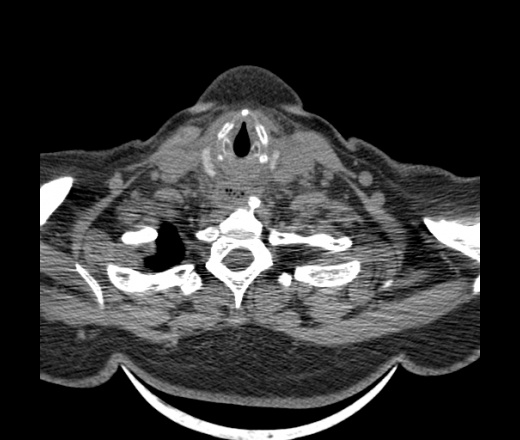

Женщина поступила в х/о спустя 4 дня после того как при употреблении карася подавилась костью.

Наличие газа в средостении на протяжении тел С2-С6 (медиастинальна эмфизема); рыбная кость на уровне тела С6.

При всем уважении, но говорить о медиастинальной эмфиземе, оценивая мягкие ткани шеи, как-то слишком резко. На мой взгляд, это ретрофарингеальное пространство.

Согласен с Вами; конечно, наличие газа в клетчатке ретрофарингеального пространства (затмение с опечаткой..). К сожалению, процесс "продвигается" к медиастиниту. Но почему никто, не отмечает наличие рыб. кости; или это для Всех очевидно?

Кость то мы сразу выявили, размеры где то 17*2мм, но ее так и не получается найти в этой каше